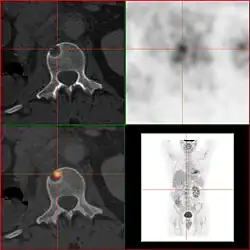

Knochenmetastasen

Knochenmetastasen unterschiedlicher Tumorerkrankungen können mit PET/CT sehr gut nachgewiesen werden. Das Verfahren ist sensitiver als die SPECT und erheblich sensitiver als die planare Skelettszintigrafie, jedoch auch aufwändiger und somit teurer. Je nach Tumorentität werden unterschiedliche Tracer verwendet, meist jedoch FDG und Natriumfluorid, beim Prostatakrebs auch 11C- oder 18F-Cholin. Metabolische Aktivität des Tumors ist mit Hilfe des Tracers FDG, die Reaktion des Knochens auf den Tumor mit der Natriumfluorid-PET/CT meist gut darstellbar (siehe Bildbeispiele).[33]

FDG-PET desselben Patienten: Die osteolytische Knochenmetastase im Halswirbelkörper reichert FDG nicht an und ist nur im CT erkennbar. Die beiden weiteren Knochenmetastasen in der Lendenwirbelsäule werden dagegen auch in der FDG-PET/CT dargestellt. -

Natriumfluorid-PET/CT desselben Patienten: Die osteolytische Knochenmetastase in der Halswirbelsäule zeigt einen extremen Uptake und ist klar erkennbar. Die beiden weiteren Knochenmetastasen in der Lendenwirbelsäule stellen sich in der PET/CT-Aufnahme ebenfalls sehr gut dar. -

Vergleich derselben Läsion des vorgenannten Patienten: Die FDG-PET/CT-Aufnahme zeigt die Stoffwechselaktivität des Tumors. -

Vergleich ein und derselben Läsion des vorgenannten Patienten: Die Natriumfluorid-PET/CT-Aufnahme zeigt die Stoffwechselaktivität des Knochens als Reaktion auf den Tumor.